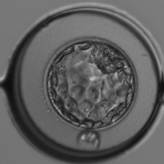

胞胚腔と呼ばれる腔が確認できるものを“胚盤胞”といいます。

胚盤胞になった受精卵は

ガードナー分類を使用しグレードをつけていきます。